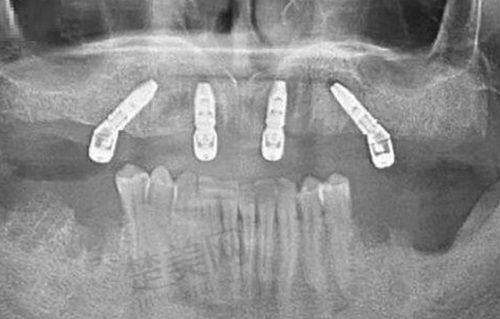

在设备上,医院注重引进高端的医疗设备和技术,配备了数字化口腔成像系统、口腔CT扫描仪、激光治疗设备等多种可靠的口腔诊疗设备,能够支持复杂的种植牙手术和其他口腔治疗项目。

种植牙是平凉三旺口腔医院的特色项目之一。医院在种植牙技术上具有多种优势,有即刻种植、微创种植牙、普通种植、全口/半口牙颌种植、微创即刻种植等多种种植方式可供选择。医生团队经验多,能够根据患者的具体情况制定个性化的种植方案。同时,医院配备的口腔CT扫描仪等高端设备,能够精细地为种植牙手术提供支持,提高手术的成功几率。

徐旺医生:擅长治疗部分牙列缺损、全口牙列缺损。在种植牙领域经验多,擅长即刻种植、微创种植牙、普通种植、全口/半口牙颌种植、微创即刻种植等多种种植方式,为患者带来了良好的种植牙体验。

患者D:医院的设备特别精良,医生技术也良好。我在这里做了种植牙手术,过程特别顺利,现在修复得也不错。而且医院的服务也特别周到,值得推荐。